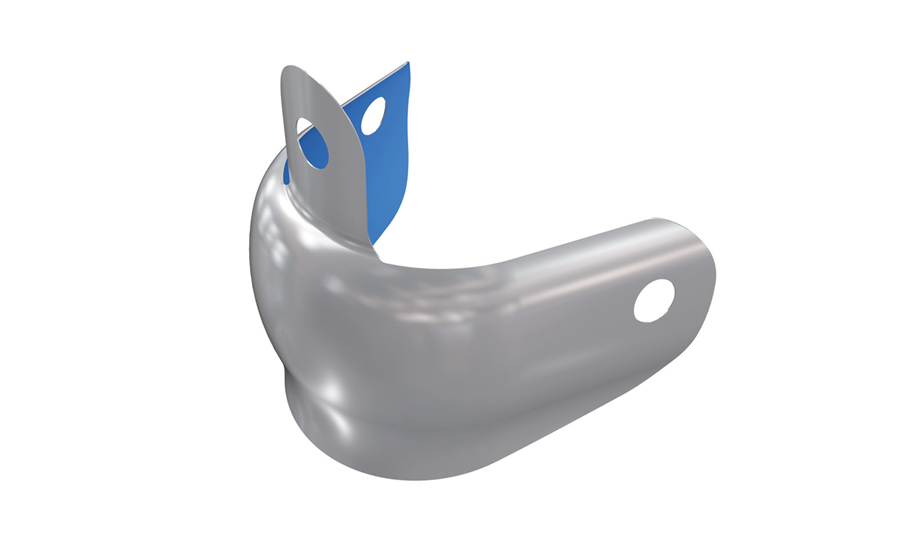

The Complete Technology-Driven Restoration

We are all restoring teeth today with a conscious effort to be minimally invasive. Our preparations are no longer extension for prevention. Everything is conservative. However, even with the decline in dental caries, and the decreased need for restorative treatment, we sometimes are still faced with complex treatment that becomes a bit of a restorative … Read more